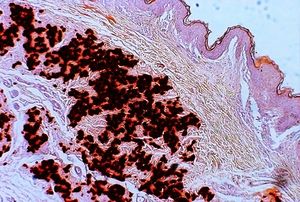

- 병변 피부의 진단적 조직병리학적 변화: 중간 및 하부 진피의 석회화된 탄성 섬유로, 칼슘 염색 양성으로 확인.